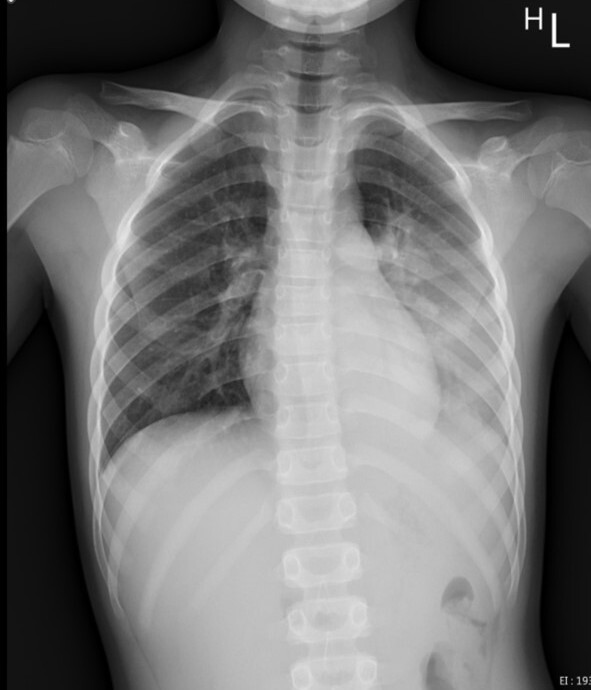

陳明群舉例,一名8歲男童因呼吸道融合病毒(RSV)合併肺炎鏈球菌及鼻病毒的感染,造成左側大葉性肺炎,就醫檢查胸部X光發現左邊肺部幾乎白了,住進花蓮慈院兒科加護病房接受治療。